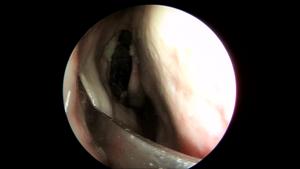

「看」吴彦桥教授讲泪前隐窝入路手术-不仅仅适用于上颌窦肿物切除